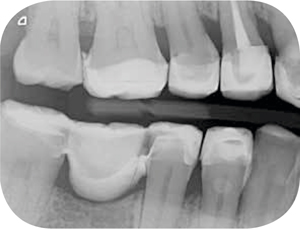

Röntgenonderzoek

Röntgenologisch onderzoek laat meerdere problemen zien. Onder andere een forse zwarting apicaal van element 12 met het beeld passend bij periapicale problematiek en een verleden van apicale chirurgie (afbeelding 8-12 ).

Afb. 9-10

Solo-opnamen van het 1e en 3e kwadrant.